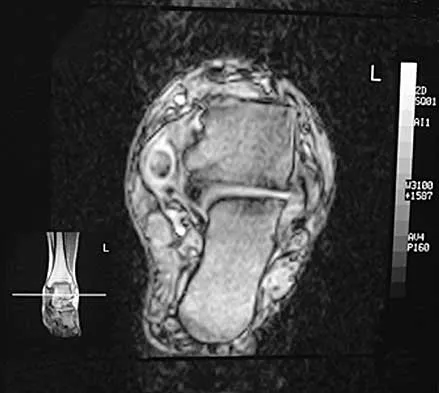

A 37-year-old woman has had intermittent paresthesias and numbness in the plantar foot for the past 6 months. She reports that the symptoms are worse with activity, and the paresthesias are beginning to awaken her at night. MRI scans are shown in Figures 6a and 6b. What is the most likely diagnosis?

Explanation